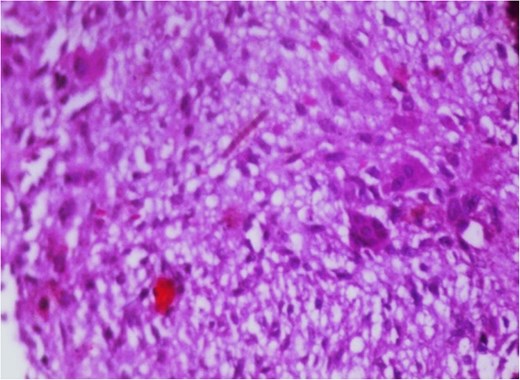

Additionally, magnetic resonance venography (MRV) confirmed a patent superior sagittal sinus with no encroachment of the lesion (Fig. 4). Differential diagnoses included dermoid cyst, eosinophilic granuloma, or benign fibro-osseous lesion. Surgical intervention involved en bloc excision under general anesthesia. A curvilinear incision was made over the mass, followed by subperiosteal dissection, which confirmed the lesion’s confinement to the diploë. Intraoperative frozen section analysis was not performed due to the lesion’s benign radiological features. Histopathological examination confirmed NOF, demonstrating ectodermal inclusion, cellular stroma of spindle-shaped fibroblasts arranged in a prominent storiform pattern, and scattered osteoclast-like giant cells. Notably, no evidence of mitotic figures, nuclear atypia, or necrosis was observed (Figs 5–7). The margins were free of lesional tissue. Postoperatively, the child resumed oral intake within 4 hours and was discharged on postoperative day 2 with analgesics. At the 6-month follow-up, the wound had healed without complications, with no recurrent lesion.

Photomicrograph in a case of NOF showing interlacing bundles of spindle-shaped fibroblasts in a storiform manner, H&E × 100.